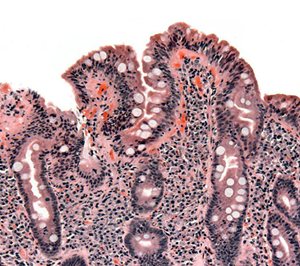

- La enteropatía pierdeproteínas es el resultado del incremento de la permeabilidad de la mucosa a las proteínas séricas, secundaria a la erosión o ulceración de la mucosa gastrointestinal, con la subsiguiente pérdida de proteínas, y a la obstrucción linfática o a ambas, como sucede en la ENTEROPATÍA SECUNDARIA A PATOLOGÍA TUMORAL.

Enteropatía no-celíaca (www.gastroenterologyupdate.com.au)